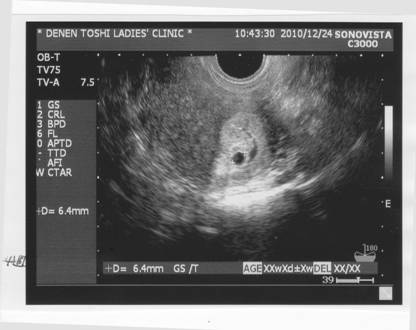

「3度目の正直」である。

第2子をと考えてから、2回の流産を経験した。

1回目、順調に週齢を積み重ねていたはずが、

「心臓の音が聞こえないって言われた・・・。」

おママからの、いや医師から宣告されたその言葉は私達の虚を突いた。

頭上からずっぽりと暗闇に多い被られ、

しかし事の次第を理解するのに少し時間がかかった程である。

Sだけでさえ非常な苦労があったのに、まだ来るか・・・。

前ぶれはあった。

原因不明の出血があり、最後までその血腫は小さくなることがなかった。

結局そのまま大きくなる事は叶わなかった。

心身の傷が癒え、「次ダメだったらもう諦めよう」ラストチャンスと望んだ2回目。

しかしまたもや希望は早々にうち消されてしまった。

再び忌まわしい出血が起こり、小さな命の火は大海に消されてしまったのだ。

しかしおママは流産後の子宮収縮の痛みと出血に耐えながら、

早期に3度目を決めていたと記憶する。

この2回目があまりに早すぎたので、流産の確率10%の範囲、

つまり胎児何らか先天的な異常があった?

仕方のないそれであると思われること。

そして何よりまだやり残したこと(手段)がある、と・・・。

まず1回目、2回目の出血の原因となりうるであろう、ポリープ摘出だ。

そして通常は3回流産を繰り返した場合に受ける検査を、この2回目の段階で受けた。

検査の結果、血液検査で凝固因子の一種であるTATが異常に高かったが、その疑念も払拭した。

これで条件は整った。

レディースクリニックに。

エコーでも、確認できた。 しかしあの黒い帯、 出血もまたおいでなすった。 心配は尽きない。 |